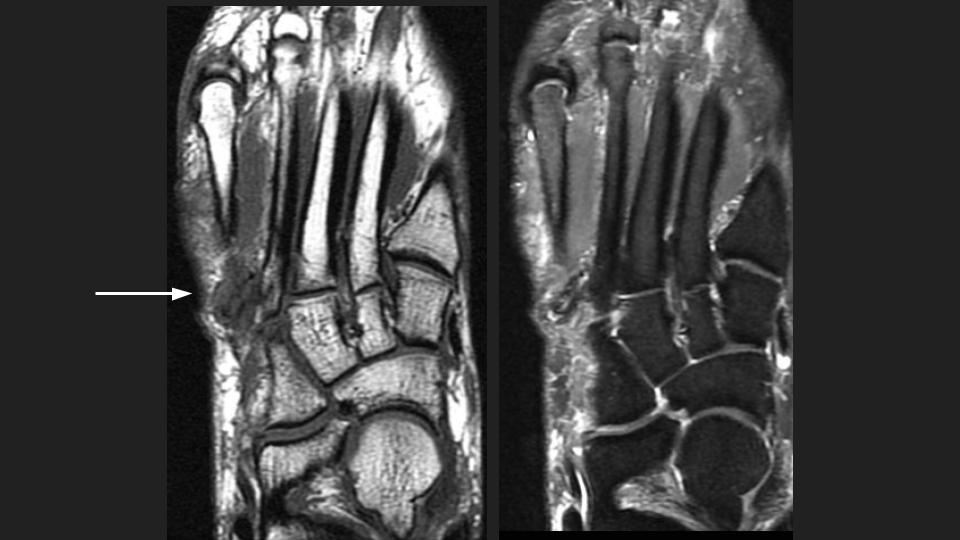

Figure 1 for case peroneus tertius ( RID2915 )

Figure 1

Area of pain indicated by markers surrounds the insertion of the Peroneus Tertius tendon onto the base of the 5th and likely also 4th dorsal MT base. The tendon is thickened with intrasubstance intermediate T1 and bright T1 signal. This is the insertional tendinosis of the peroneus tertius, with probable superimposed partial intrasubstance insertional tear suggested in the Sag fat sat images. The reference does not say much about the insertion, but includes some anatomic references that indicate variation in the insertion site at the 5th and sometimes 4th and 5th MT base. Reference article.